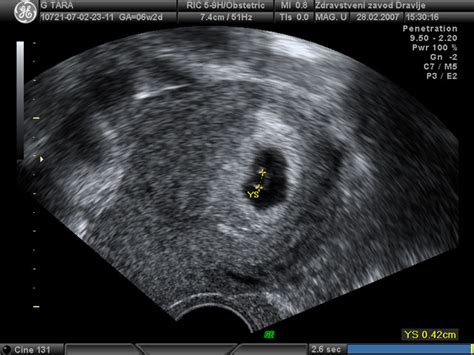

Intenziven Razvoj Ploda:V petem tednu nosečnosti začne srček utripati, kar je mogoče videti z ultrazvočno preiskavo. Plod je v velikosti sezamovega zrna, vendar se že formirajo ostali organi, kot so želodec, jetra in ledvice, ter sistemi organov, kot so žile, živčevje in prebavila. V šestem tednu se v srčku že oblikujejo štiri votline, začnejo pa rasti tudi rokice in nogice.

Prvo Trimesečje: Ključni Pregledi:Prvo trimesečje vključuje pomembne preventivne preglede. Med njimi so laboratorijske analize krvne slike, krvnega sladkorja na tešče, določitev krvne skupine in RH faktorja, test na toxoplasmo gondii in sifilis. Ultrazvočna potrditev nosečnosti se opravi do 11. tedna, med 11. in 14. tednom pa se priporoča pregled nuhalne svetline in dvojnega hormonskega testa.